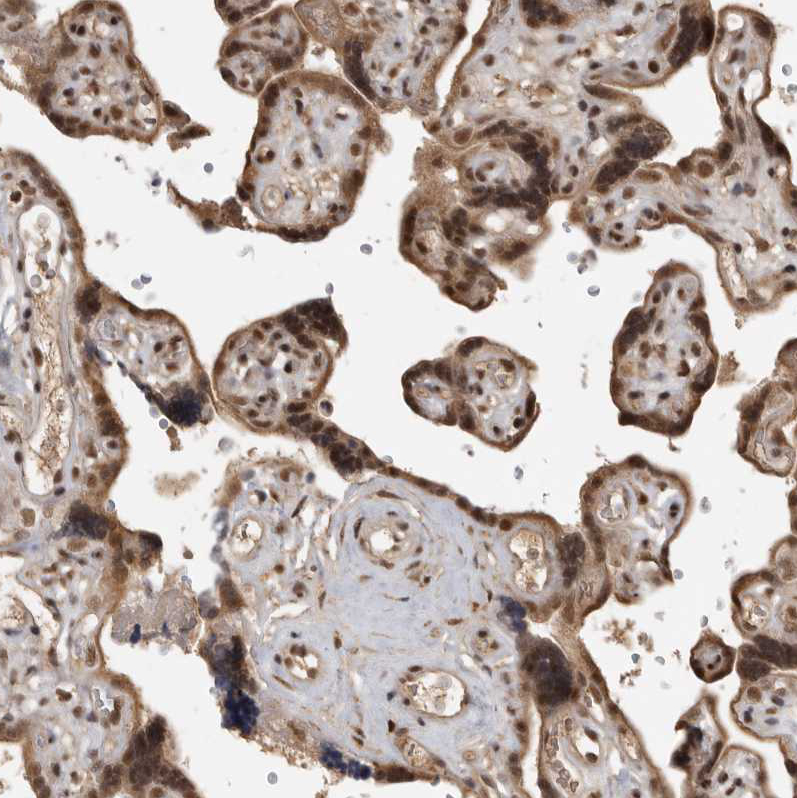

Immunohistochemical staining of human cerebellum, liver, placenta and testis using Anti-CBLL1 antibody HPA026699 (A) shows similar protein distribution across tissues to independent antibody HPA021773 (B).